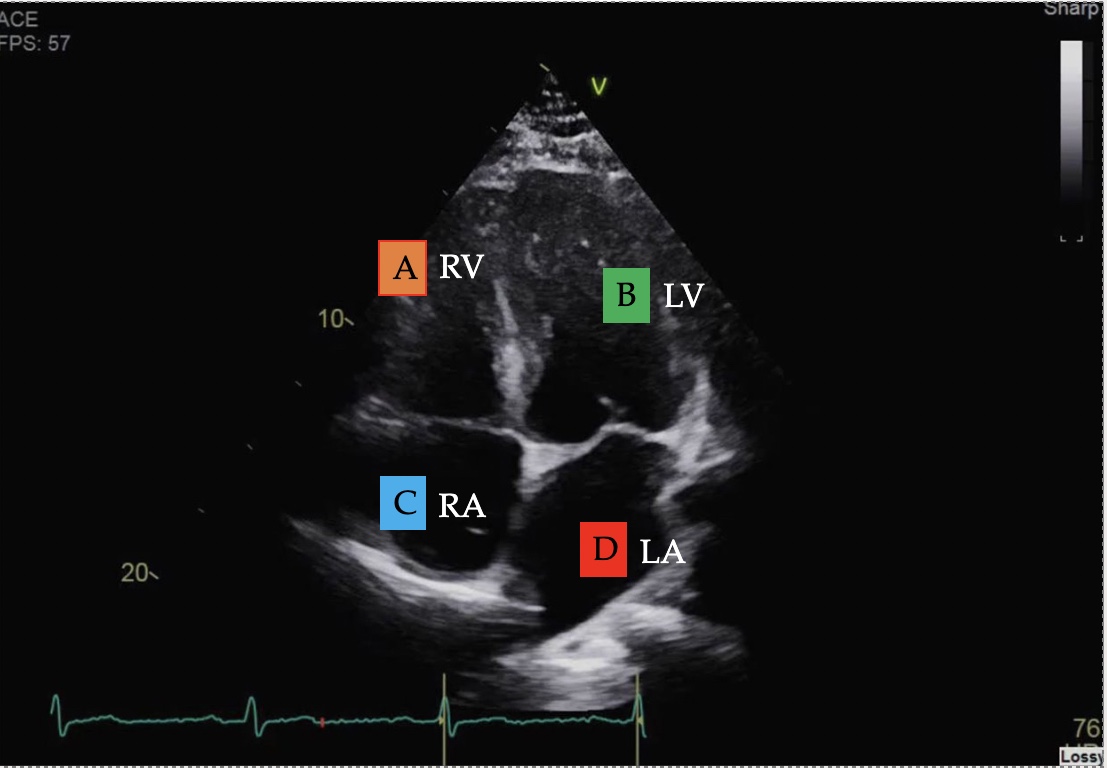

Identify the view and structures

Apical 4 chamber